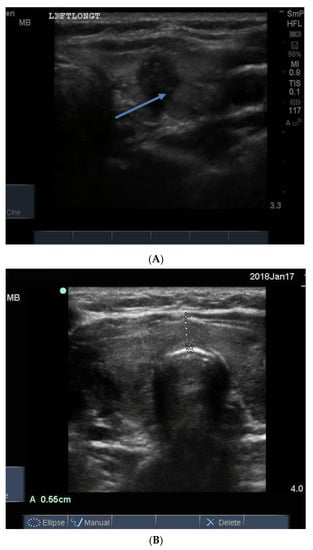

The normal gland does not contain any calcification. The presence of calcification in association with nodules generally indicates that the nodules are long standing and therefore likely to be benign. However, breaks in the wall of a calcified nodule suggest that the nodule is a cancer which has invaded into the surrounding thyroid tissue and is considered a suspicious feature of a nodule []. Calcification is sometimes seen as spots or sheets scattered throughout the thyroid. Calcification surrounding a thyroid nodule, giving it the appearance of a “bone ball”, can be felt as a hard, mobile lump on neck palpation that is crunchy on biopsy. Chronic linear or egg shell calcification is associated with shadowing because the ultrasound waves are unable to pass through calcified tissue (Figure 8A,B). Calcification is also seen in the thyroid of patients with chronic Hashimoto thyroiditis and Graves’ disease.

Figure 8.

In (A) linear calcification in the anterior aspect of a benign 15 mm nodule is seen as a curved bright hypoechoic shelf (arrow) that blocks the transmission of the ultrasound waves, so the nodule behind appears to be very hypoechoic, as in a cyst. In (B) is seen a small hypoechoic calcified nodule (upper arrow) and below it, a larger nodule with linear calcification in its anterior surface (lower arrow).